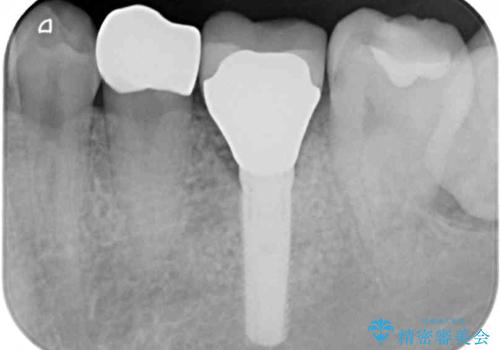

- 奥歯がしみて痛いとのことで来院された患者様です。

既に複数箇所の修復が行われていたため、オールセラミッククラウンにて補綴をすることとしました。

以前装着した修復物が不適であり、歯肉が腫れていましたが、仮歯を装着したことで腫れは解消されました。

歯の痛みだけでなく、歯肉の腫れも改善され、患者様には大変満足していただきました。